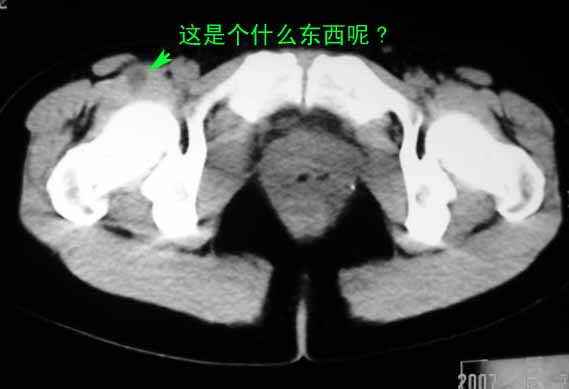

标题: CT8123:女46岁,左下腹胀痛不适1月,以前曾有月经过多史,现已 [打印本页]

标题: CT8123:女46岁,左下腹胀痛不适1月,以前曾有月经过多史,现已

考虑子宫们内膜癌并右侧腹股沟淋巴结转移

子宫们内膜癌或子宫颈癌体部浸润并右侧腹股沟淋巴结转移